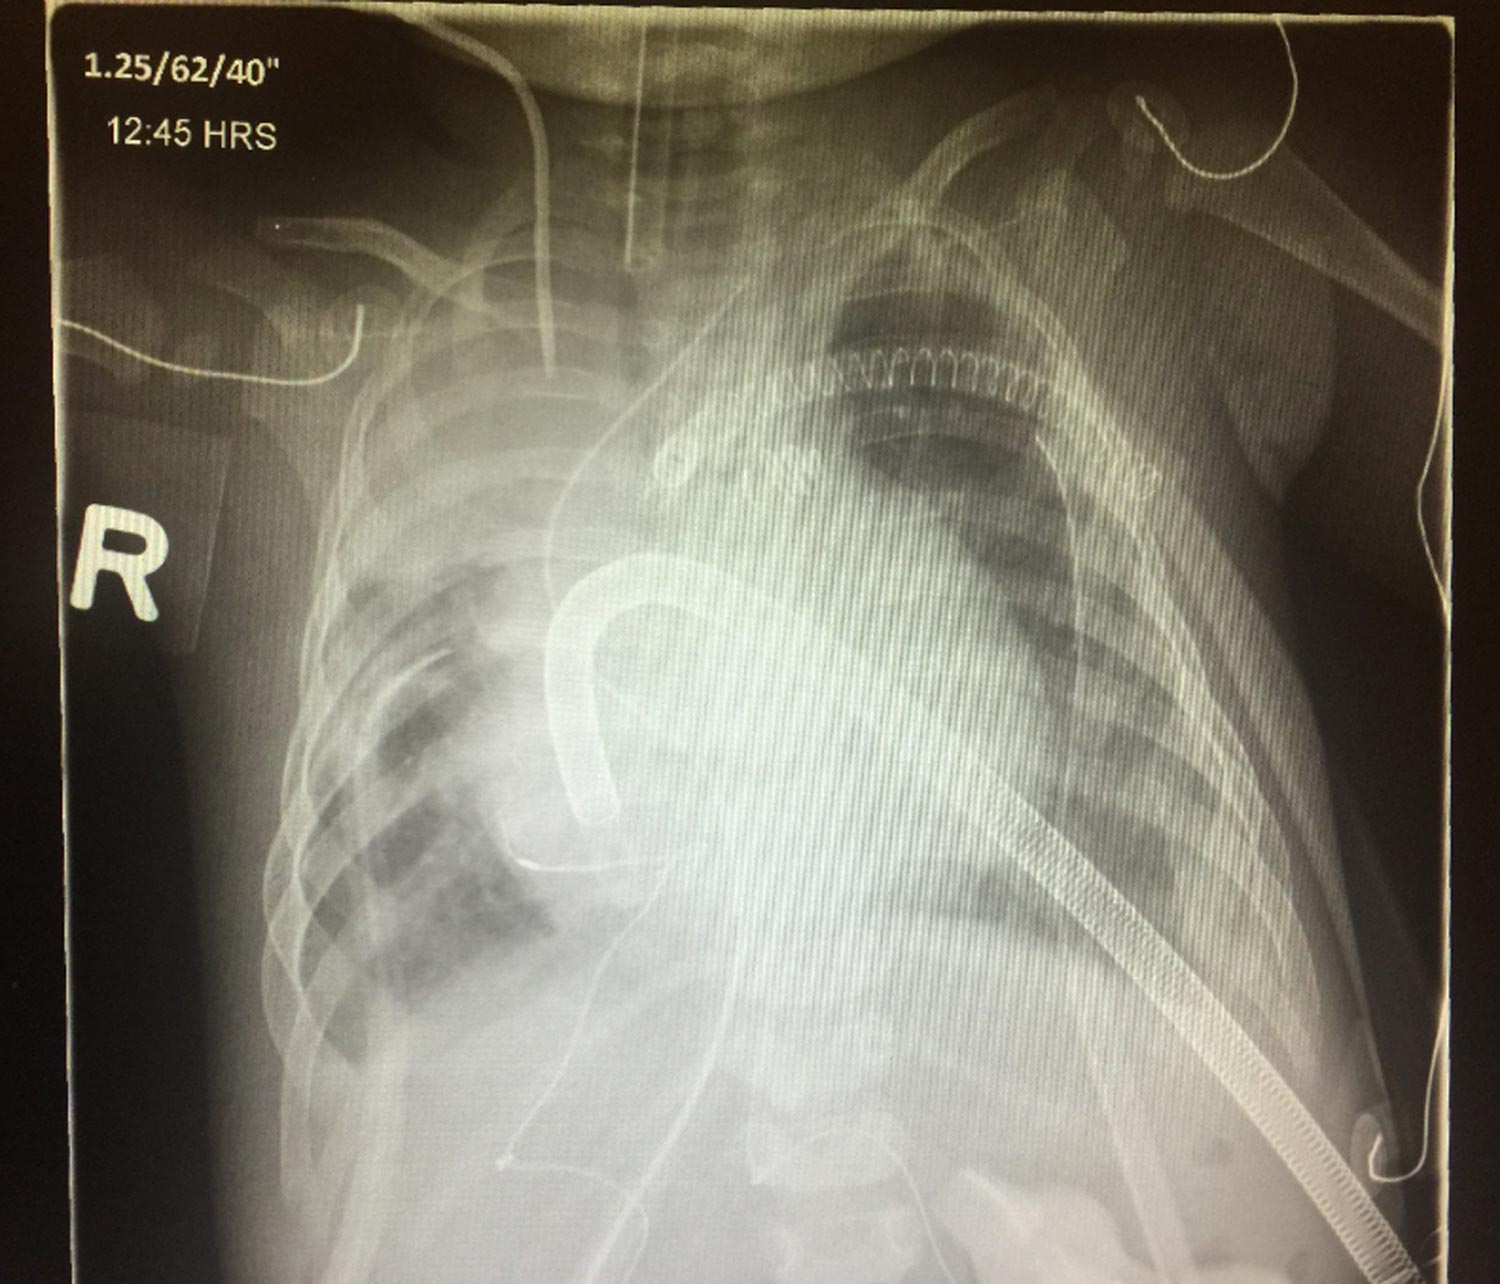

Congenital heart defects affect one percent of live births and are notoriously difficult to understand in their 3-dimensional (3D) form. Current educational practice for residents (junior doctors) leans heavily on memorization and diagrammatic representations of CHD. Patient education for visualizing what congenital heart defects look like relies on 2D illustrations, sourced from Google. There is a gap in the availability of anatomically accurate learning tools to understand CHD. This presents an opportunity to develop and document the design of a curriculum focusing on concrete forms of visualization.